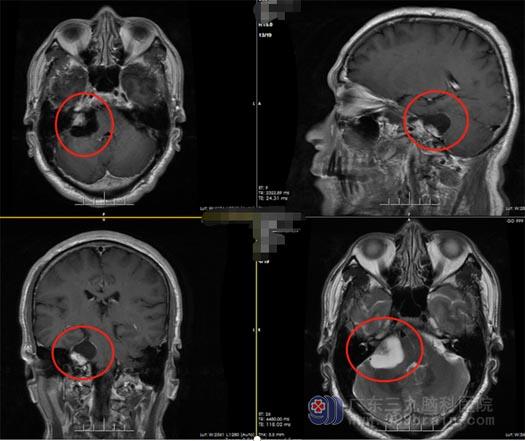

钟先生用蓝牙耳机听歌时,总是发现右耳的声音更低,原本以为是耳机的问题,可是换了耳机还是一样的情况。钟先生去耳科检查,耳科医生却建议他去看脑外科。家人带着他来到广东三九脑科医院神经外五科,完善相关检查后,初步考虑患者是右侧桥小脑角占位,认为是听神经瘤可能性比较大。钟先生恍然大悟,原来导致他耳朵听力下降的,竟然是颅内长了瘤。

广东三九脑科医院鲁明副院长、神经外五科王国良主任高度重视钟先生的病情,反复讨论后一致同意手术治疗,而手术治疗的难点在于:手术既要切除肿瘤,又要保住患者的神经功能。患者听神经、面神经位于肿瘤的前下方,不仅位置很深,且周围结构复杂,在如此狭小的空间里,要想取出肿瘤,难度和风险可想而知。稍有差池,便会损伤颅神经、脑血管。很快,神经外五科团队为钟先生实施了右侧听神经瘤切除术。术中,医生从患者后侧行8厘米切口,见肿瘤位于右侧桥小脑角,予显微镜下全切肿瘤。术后钟先生神志清醒,因术中各组颅神经保护良好,钟先生无明显颅神经损伤的阳性体征表现,恢复良好。

▲术前